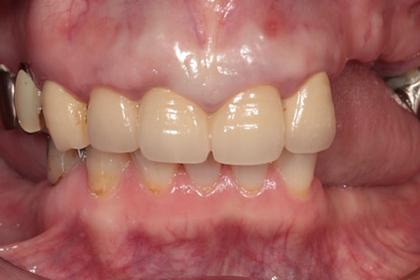

総合的な審美治療

Before

After

基礎データ 30代女性

治療期間 2003〜2009年

治療費 144万(矯正治療の費用は他院にて請求)

主な治療 歯列矯正・抜歯・軟組織移植・クラウンブリッジ補綴

治療計画 不正なクラウンを除去、保存できない歯を抜歯し、正しい噛み合わせを作れるように外科矯正を含んだ矯正治療を行う。

矯正治療後、前歯部の吸収した組織を増大し、クラウンブリッジを作成した。